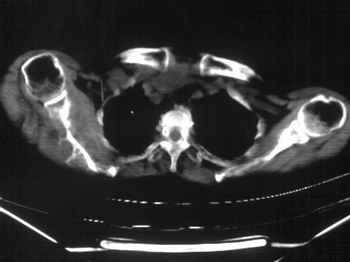

以下是引用zhangxu5888在2007-9-11 16:25:00的发言:[br]有侧肩胛骨溶骨性破坏且见软组织成分,增强软组织强化明显,中央见低密度坏死区!根据病史10年,考虑良性肿瘤恶性变!性质待定!

以下是引用老爱克斯新网客在2007-9-11 18:22:00的发言:[br]应该是良性肿瘤恶变,但因晚期破坏严重不能见到原来肿瘤征象无法判断,